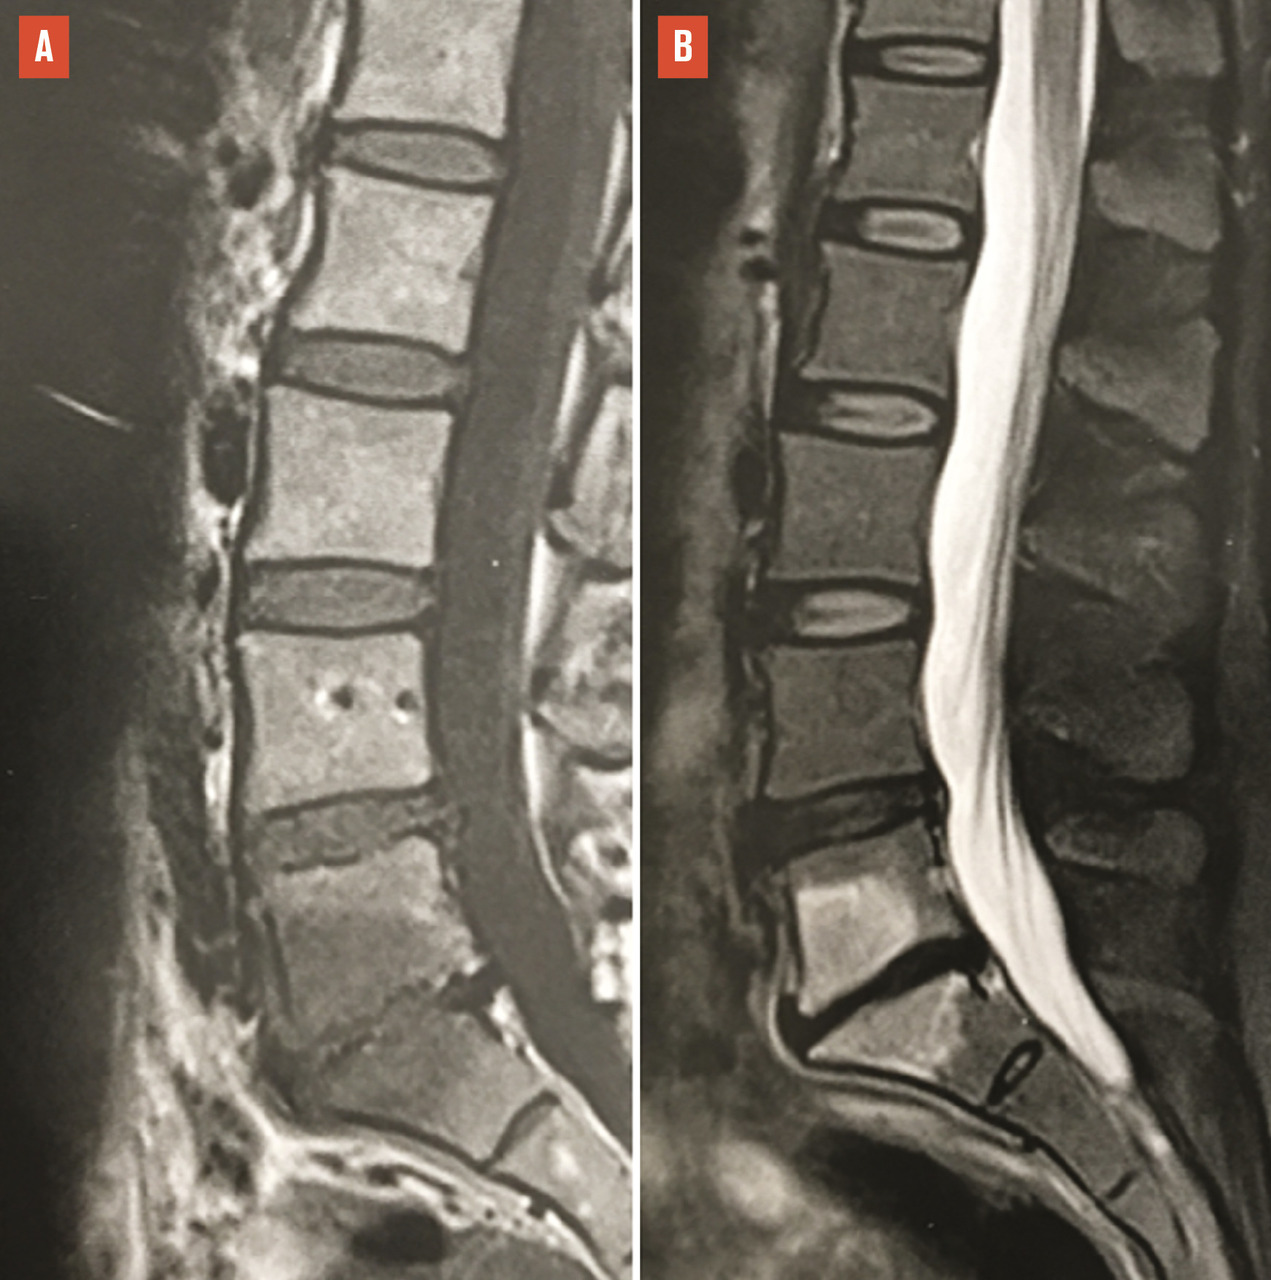

La plupart des rhumatologues français réalisent les injections de corticostéroïdes dans les articulations interapophysaires postérieures pour passer un cap douloureux aigu, dans les cas où l’examen clinique ou la ­présence d’un hypersignal « œdémateux » en IRM, sur les séquences ­pondérées en T2 avec suppression du signal de la graisse (fig. 4), suggè­rent qu’elles peuvent être en partie responsables des douleurs. Cependant, des essais randomisés n’ont pas pu mettre en évidence de supériorité des injections de corticoïdes dans les articulations postérieures, par rapport à des injections intra-arti­culaires de sérum salé.10, 11 Par ailleurs, il n’y a pas de place, d’une façon générale, pour un geste percutané intradiscal dans les lombalgies chroniques communes, car leur cause est multifactorielle et toujours incertaine.

Le cas des discopathies dégénératives dites « actives », avec un signal « œdémateux » (hypersignal T2) des plateaux vertébraux en IRM (« Modic 1 ») est particulier (fig. 4). C’est le seul signe radiologique qui soit bien corrélé aux lombalgies. D’où la tentation de traiter les patients par des injections locales de corticoïdes.12 Un essai randomisé chez des lombalgiques exprimant un signe de « Modic 1 » a montré que l’efficacité d’une injection intradiscale de corticoïdes, sur la lombalgie, est supérieure à celle d’une injection intradiscale de sérum salé à un mois (-2,4/10 points sur une échelle visuelle analogique douleur), mais pas à trois mois ou ultérieurement.13 Ce bénéfice paraît trop éphémère pour justifier l’usage de cette voie d’administration, qui comporte un risque, faible mais ­certain, de spondylodiscite infectieuse iatrogène. Dans cette situation, il paraît plus raisonnable de se limiter à des injections épidurales locales de corticoïdes ou à une faible corti­co­thérapie per os.